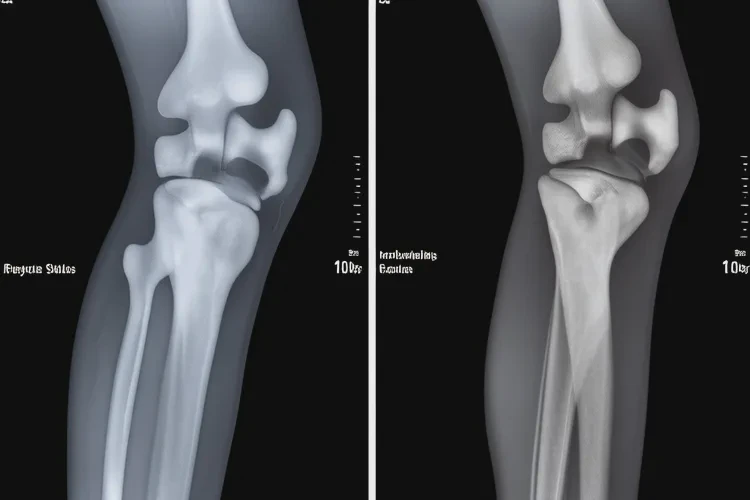

治療前需進(jìn)行系統(tǒng)評估,包括病史采集、體格檢查及影像學(xué)檢查(如X光、MRI)。醫(yī)生會根據(jù)Kellgren-Lawrence分級判斷關(guān)節(jié)炎的嚴(yán)重程度,為制定個性化治療方案提供依據(jù)。

河南濮陽康復(fù)科治療骨關(guān)節(jié)炎要多少錢(圖1) 河南濮陽康復(fù)科治療骨關(guān)節(jié)炎要多少錢(圖2)